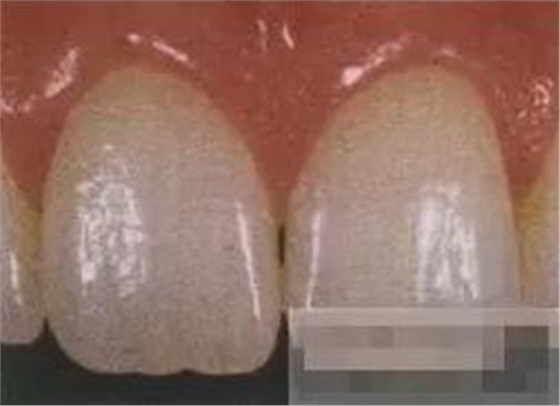

【檢查】12,11,21,22,均行玻璃離子充填,各牙不同程度部分充填物脫落,探(—),叩(—),冷刺激無(wú)反應(yīng),無(wú)松動(dòng),牙齦顏色粉紅,質(zhì)地堅(jiān)實(shí)而有彈性,點(diǎn)彩正常,牙結(jié)石(—);牙髓活力測(cè)試無(wú)反應(yīng)。

【診斷】12,11,21,22牙體缺損